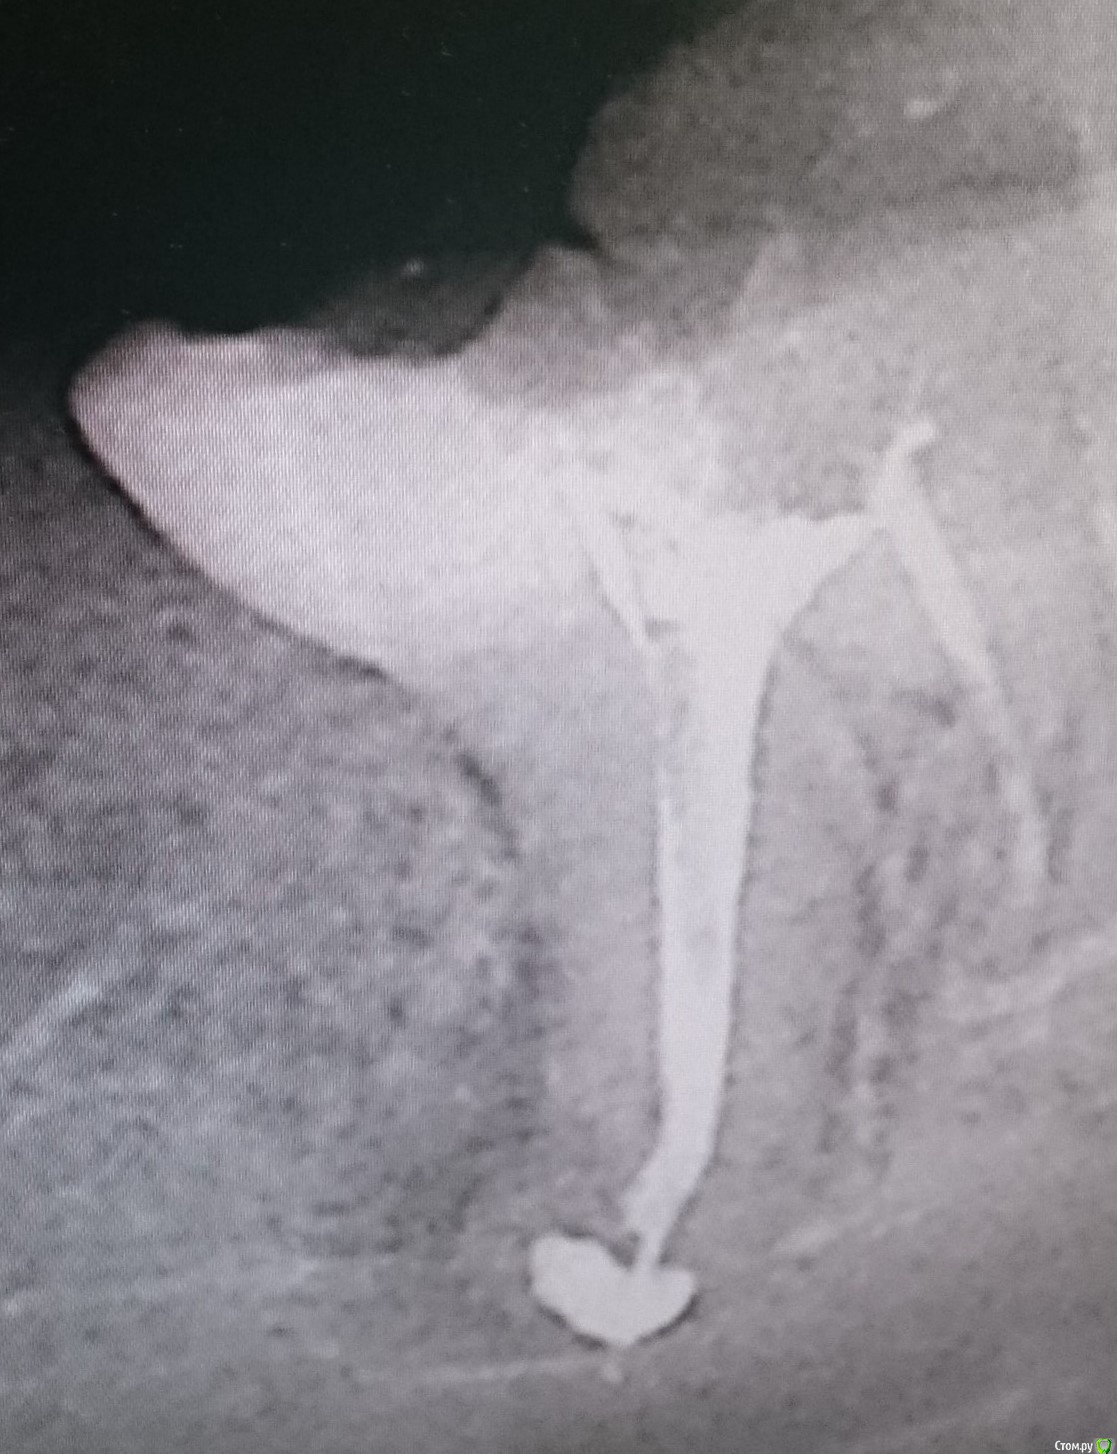

y2006 Опубликовано 22 сентября, 2015 Поделиться Опубликовано 22 сентября, 2015 (изменено) гранулёма правой нижней восьмерки (на фото канал с иглой). первоначально каналы были пролечены 3 года назад. сейчас после обращения и попытки лечения мнения врачей расходятся удалять - лечить. за лечение : наличие зуба антагониста на верхней челюсти, наличие рядом семерки - импланта на который нельзя опереться при удалении, и мое желание сохранить зуб; за удаление: это восьмерка, наличие корней с изгибом - как следствие не гарантируют положительную результативность лечения, восьмерка частично разрушена - но пломбировка со штифтом возможна - со слов врача. по лечению сейчас старый штифт и пломба удалены и предлагается расширенный прямой проход канала с укладкой нового штифта и пломбы ( но пугает возможность перфорации корня). посоветуйте, что делать. Изменено 22 сентября, 2015 пользователем y2006 Ссылка на комментарий

y2006 Опубликовано 22 сентября, 2015 Автор Поделиться Опубликовано 22 сентября, 2015 (изменено) канал с гранулемой был ранее пройден прямо и не до конца... до обращения , в течение недели, были ощущения при кусании, теперь (после вскрытия) зуб болит и надо принимать решение, что делать Изменено 22 сентября, 2015 пользователем y2006 Ссылка на комментарий

y2006 Опубликовано 28 сентября, 2015 Автор Поделиться Опубликовано 28 сентября, 2015 (изменено) панорамы нет - есть этапы лечения -разница по времени неделя (первый с иглой, второй с "заполненной" гранулемой)посмотреть бы панорамный снимок (ОПТГ) Изменено 28 сентября, 2015 пользователем y2006 Ссылка на комментарий